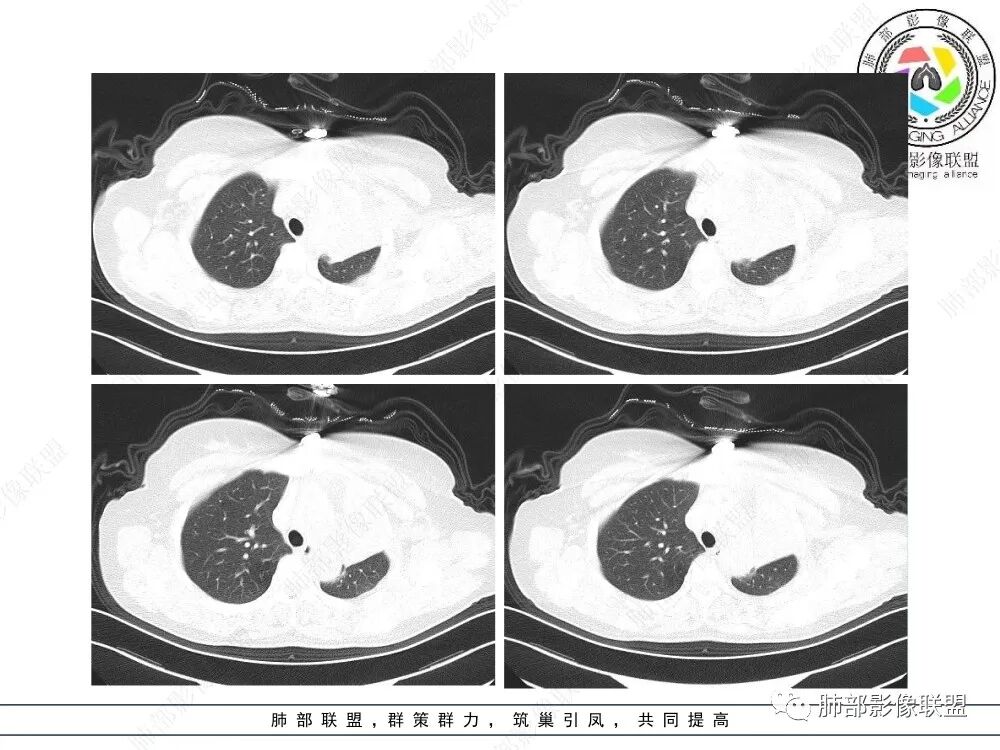

2、影像表现:正常肺背景,左肺上叶支气管腔内占位,上叶支气管截断,远端肺组织不张,强化差异衬托出肺门区结节影或块状影。增强扫描腔内占位轻中度不均匀强化,可见坏死,远端粘液栓,局部肺动脉受压、侵犯,纵膈淋巴结无明显肿大,无胸腔积液。

左上叶支气管堵塞,远端肺不张、实变。

女,59,咳嗽4月。胸部CT:左上叶体积缩小,左肺上叶不张,叶裂平直回缩,左上叶支气管腔内见低密度软组织影,向腔内突入,远端粘液栓。增强血管走行清楚,腔内肿物中度强化。考虑左上叶腔内肿瘤伴左上叶不张,粘表?鳞?鉴别TB肉芽肿。